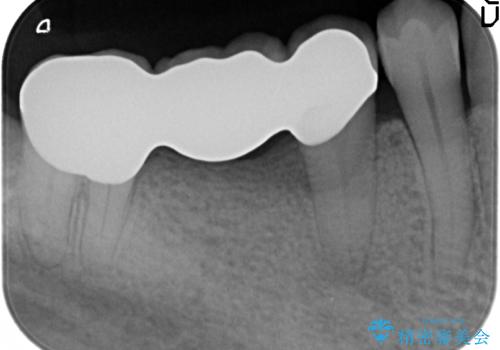

矯正治療後、右下のインレーブリッジおよび左下の銀歯のやりかえを行なっています。

右上の八重歯は、右上の奥歯を矯正用ミニスクリューを用いて遠心移動を行い解消しました。